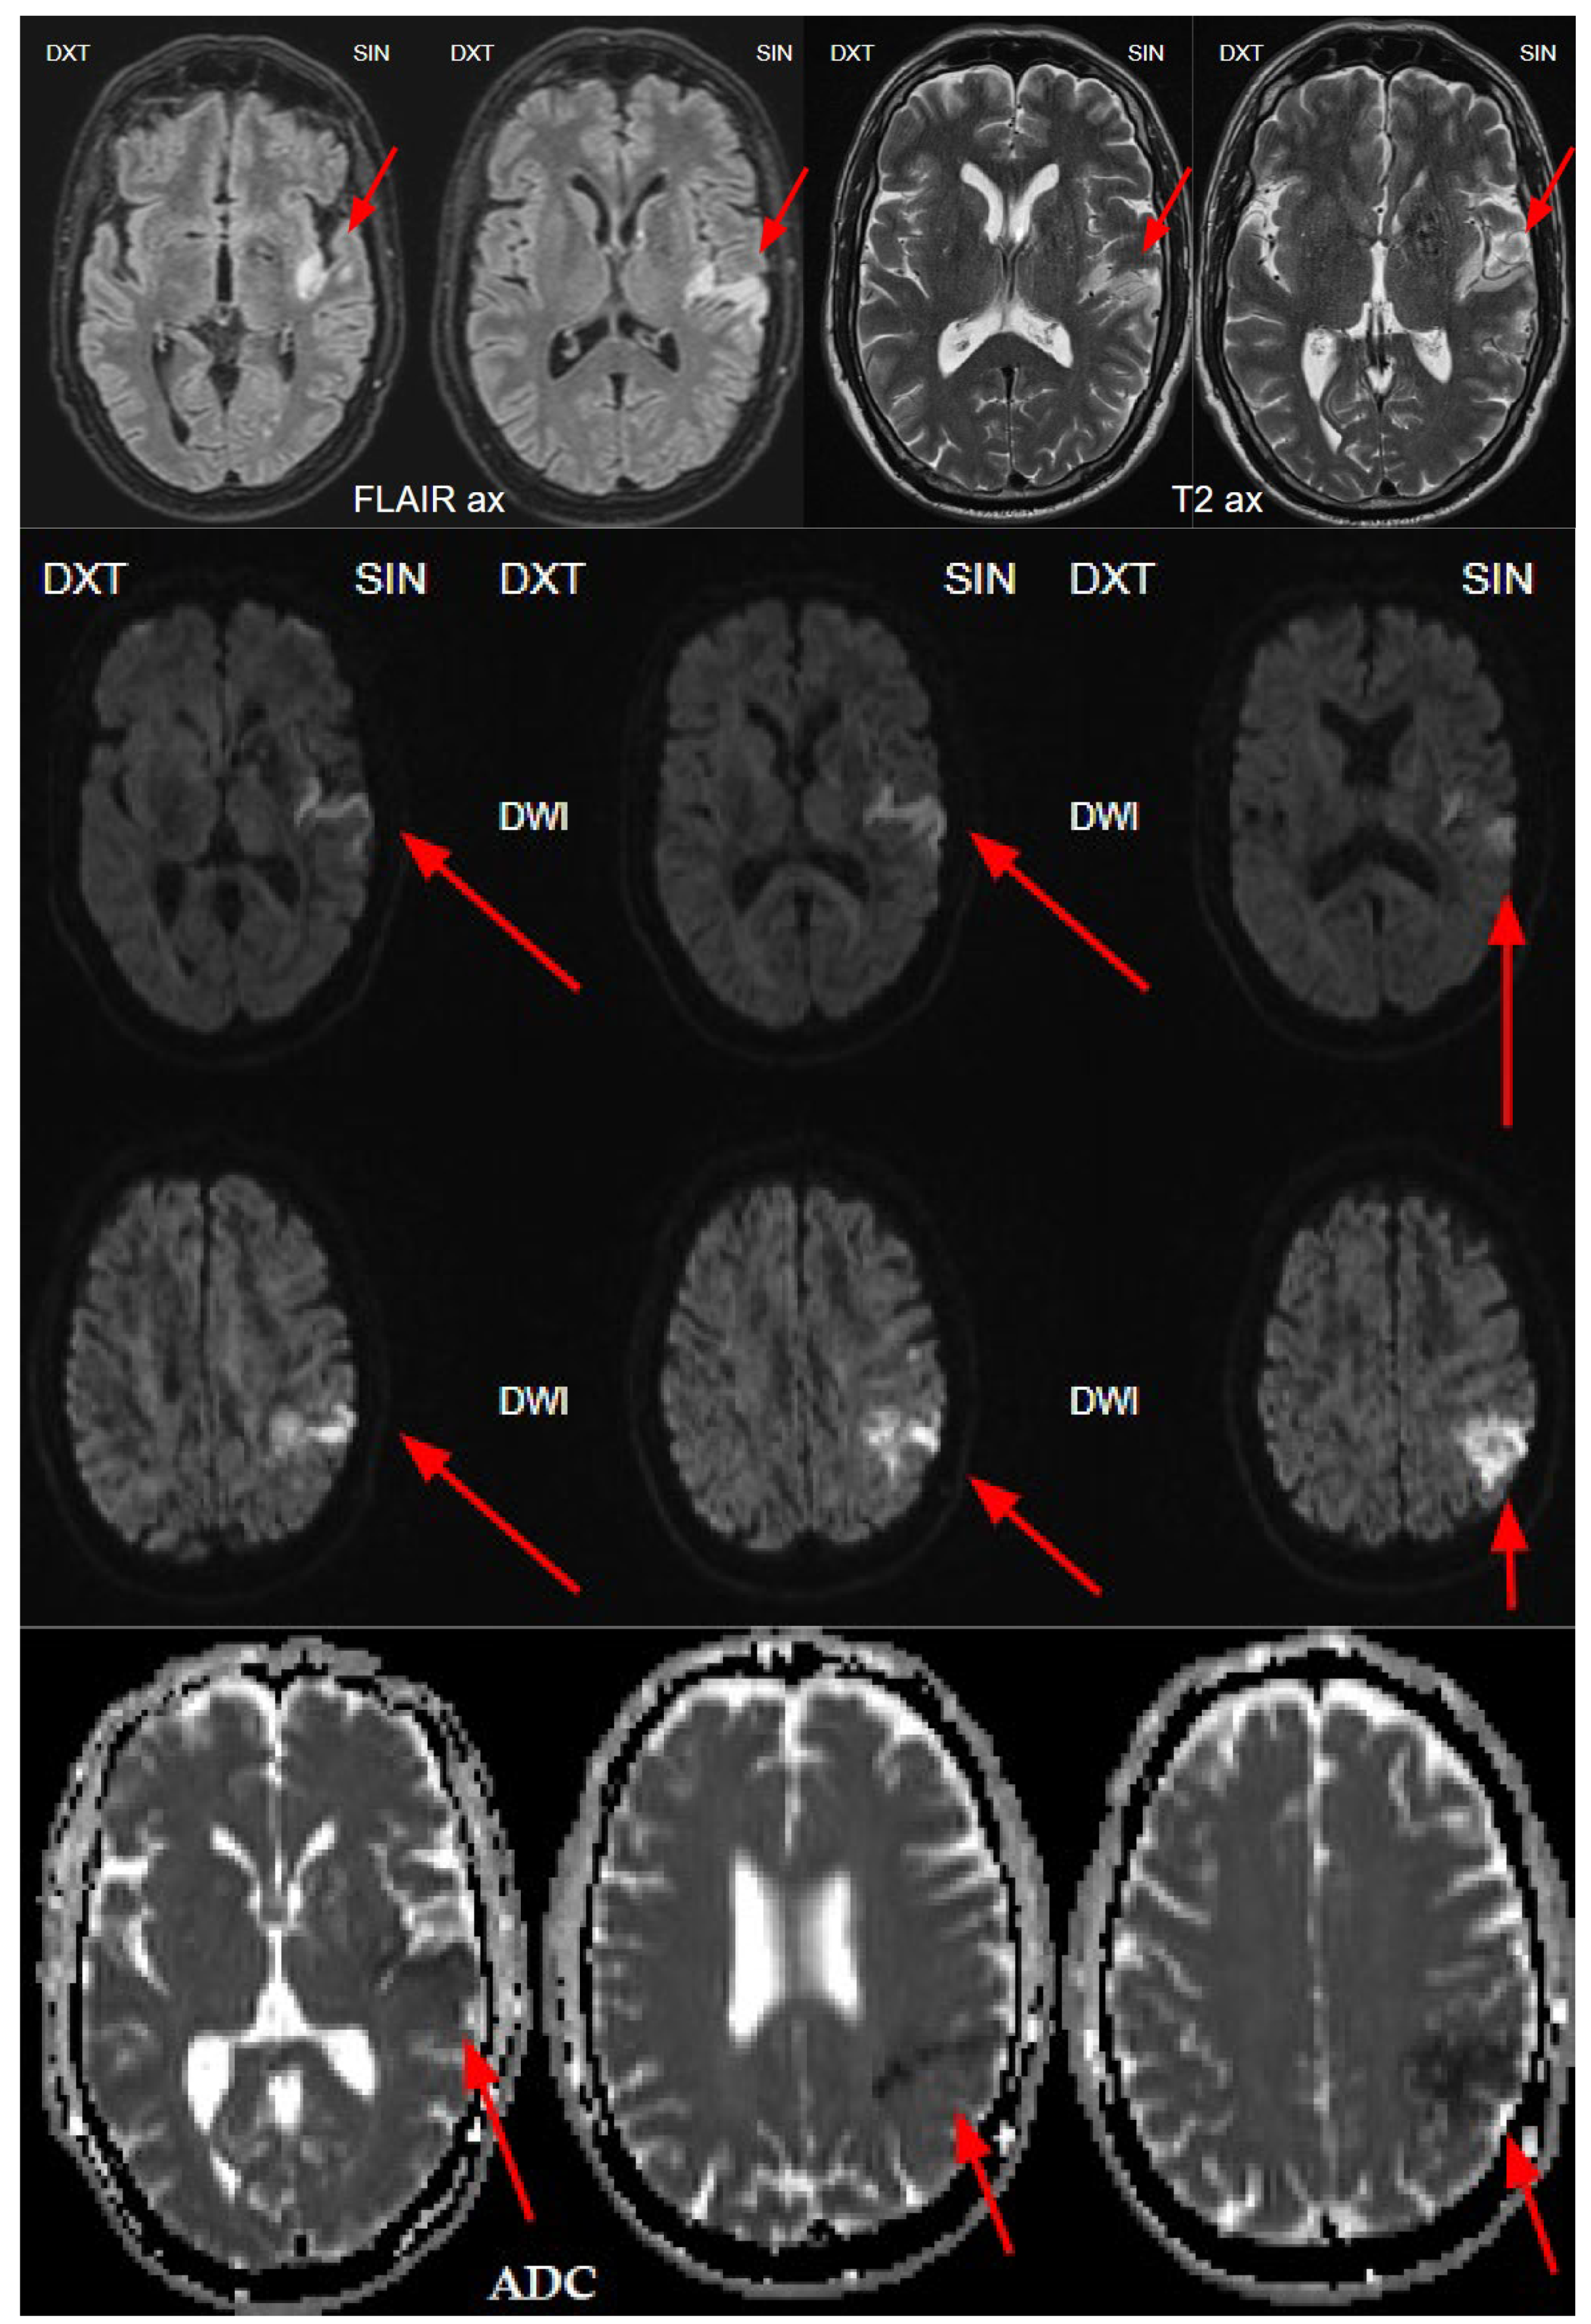

Figure 6. The next day's magnetic resonance imaging (MRI) with fluid-attenuated inversion recovery (FLAIR) and T2-weighted sequences reveals acute ischemia in the left insula and left parietal lobe, and upper gyrus of temporal lobe corresponding to the lesion seen on CTP and consistent with the territory of the left middle cerebral artery (MCA), M2 segment. Diffusion weighted imaging (DWI) sequence showing restricted diffusion on left side insula, left parietal and temporal lobe with low apparent diffusion coefficient (ADC) map value, which corresponds to acute infarction of the middle cerebral artery territory of the left side M2 occlusion.

The next day, a neuroradiologist reviewed a control followup NECT, that demonstrated an ischemic lesion localized to the left insula, predominantly involving the left parietal lobe and the superior gyrus of the left temporal lobe (Figure 1). Additional radiological findings included a hyperdense artery sign, characteristic of acute thrombosis, and basal ganglia calcification on the left side, warranting further investigation to clarify the underlying aetiology. Subsequently MRI of the brain was conducted, which also revealed ischemic signs, as well as unilateral basal ganglia calcification (Figure 6). Digital subtraction angiography (DSA) was performed to clarify reasons for unilateral basal ganglia calcifications, and it confirmed the presence of a developmental venous anomaly (Figure 7).

In 2010, Dehkharghani et al. published an article demonstrating six case reports with unilateral caudate and putamen calcifications in DVA drainage territories. In all these patients, DVA was found in gadolinium-enhanced MRI and/or computed tomography angiography (CTA) or conventional angiography. They stressed out the venous hypertension as the main contributing factor for these abnormalities [22]. Moreover, they reported no symptoms referable to the basal ganglia, and patients they presented did not reveal underlying metabolic disorders or processes associated with calcium deposition [22]. In our case, the patient was a fifty-four-year-old male presenting with a sudden speech impairment and right-sided weakness. No abnormal movements were noted in this patient. Subacute stroke on the left side in the dorsal part of the insula, in the upper dorsal part of the left temporal lobe and partially in the left parietal lobe was found on NECT, and CTA revealed left middle cerebral artery (MCA) M2 occlusion. On CT perfusion (CTP), markedly decreased cerebral blood flow (CBF) and cerebral blood volume (CBV) was noted along with increased mean transit time (MTT). Subsequently, gadolinium-enhanced brain MRI was performed where small blood vessels draining to subependymal periventricular veins on T1 post-contrast was found. Due to these findings, the patient underwent following digital subtraction angiography (DSA) where venous angioma in the area of ​​the left basal ganglia was observed.